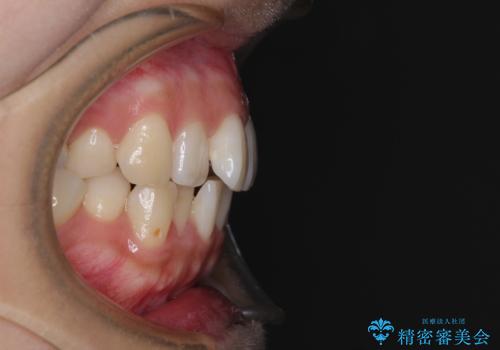

上顎歯列が下顎の歯列に対して狭小であり、一部下顎の奥歯が上顎よりも外側に位置している状態でした。

上顎の急速拡大装置を使用して上顎骨を側方に拡大することで上顎歯列を拡大し、下顎歯列も拡大できるようにすることで、歯列を整えることとしました。

上顎の拡大は、左右どちらに拡大していくのか予想が困難ですが、こちらの患者様では結果として上下正中が一致する方向に拡大され、非常にきれいな仕上がりとなりました。